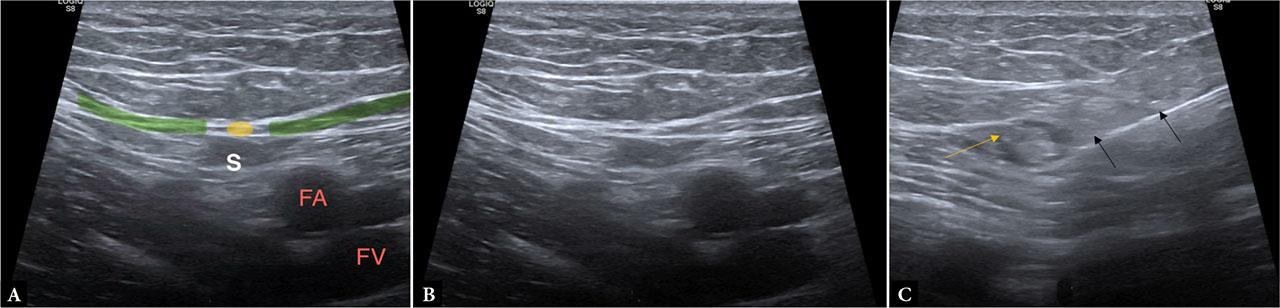

The medial femoral cutaneous nerve, a branch of the femoral nerve, supplies the medial thigh and anterior knee. Its close relationship to the sartorius muscle and the great saphenous vein provides reliable landmarks for sonographic identification. Although small, the nerve can be visualized with high-resolution ultrasound as a hypoechoic fascicular structure coursing within the superficial fascia along the medial thigh. Clinically, it is vulnerable to iatrogenic injury during medial thigh surgery or saphenous vein harvesting, and ultrasound is increasingly employed to evaluate unexplained medial thigh pain or sensory deficits in postoperative patients(20) (Fig. 10).

Images A and B demonstrate the normal medial femoral cutaneous nerve superficial to the femoral vascular bundle, distal to the femoral canal. The nerve originates from the femoral nerve and travels medially, piercing the muscular fascia (green) over the sartorius (S) to innervate the medial thigh. Image C shows a perineural steroid injection around the medial femoral cutaneous nerve within the subcutaneous plane, superficial to the sartorius, in a diabetic patient with persistent pain along the distribution of this nerve